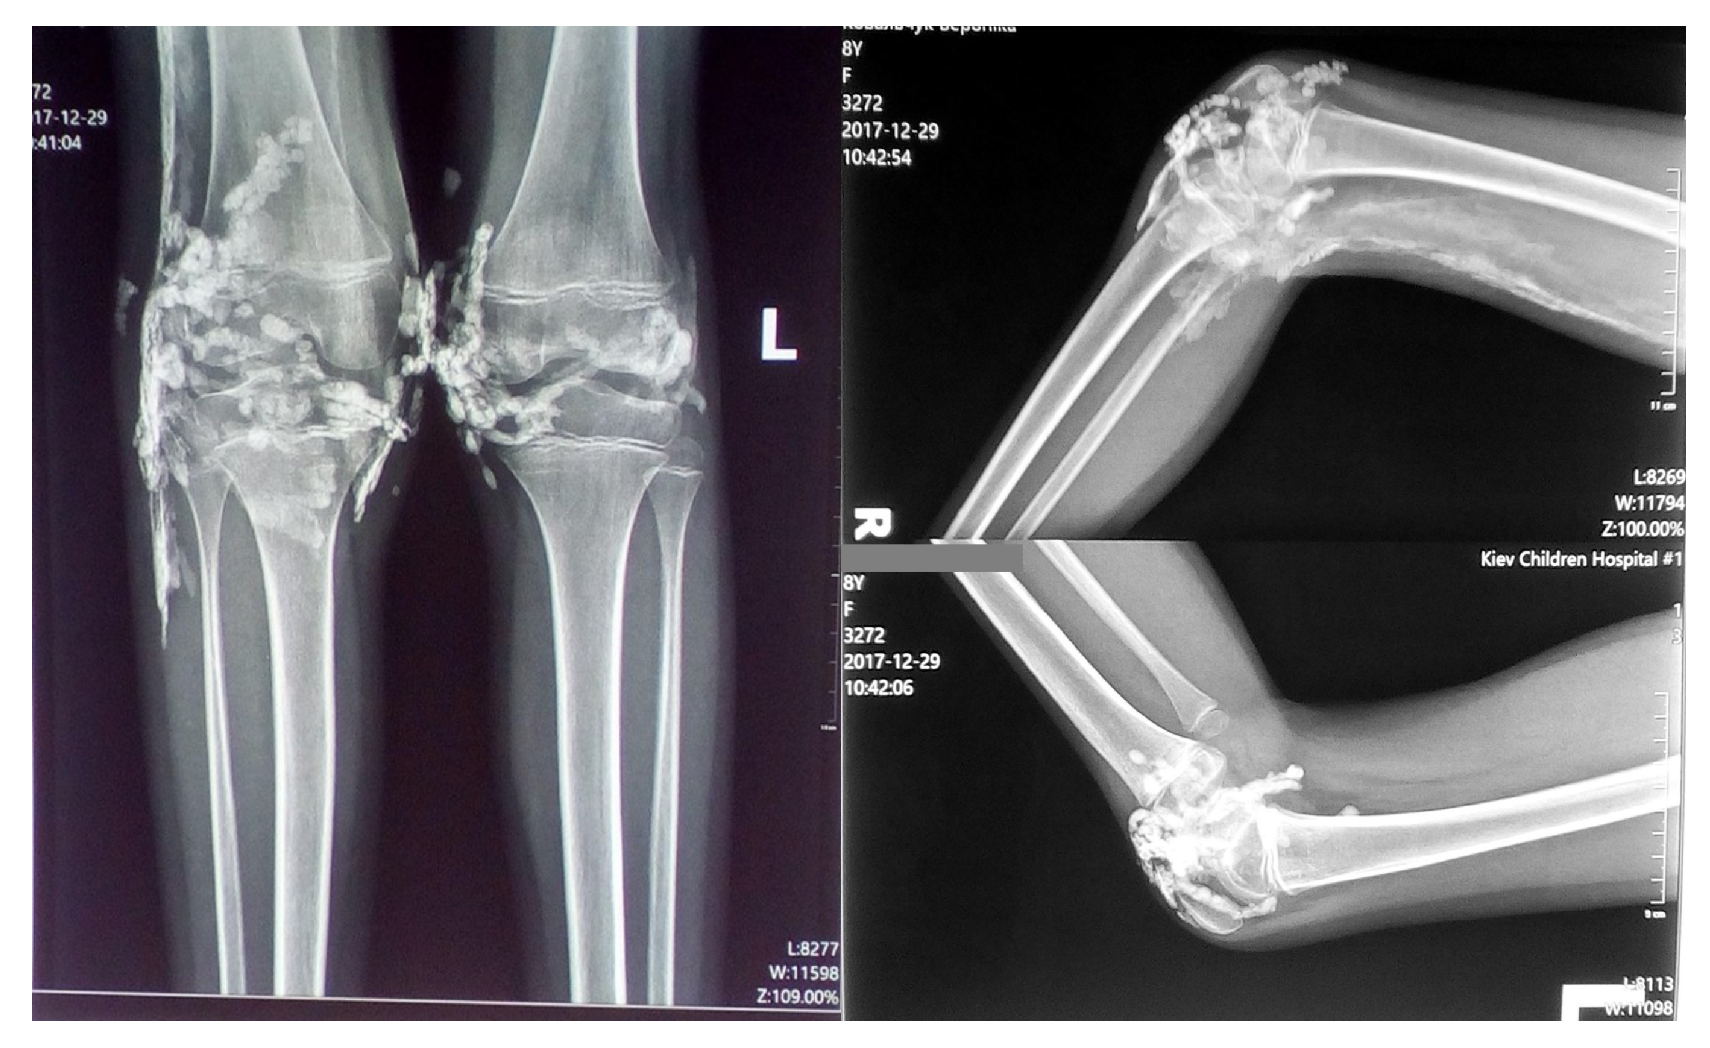

Radiographic examination of the knee joints in two projections revealed multiple small, rounded high-density shadows with well-defined, smooth contours in the projection of the knee joints and synovial recesses. Soft tissue changes were observed along the posterior-lateral surface of the distal femur and the proximal right ankle, characterized by a "feathery" pattern consistent with calcification and/or ossification (Figure 2).

Figure 2. Radiographic findings showing high-density shadows in the knee joints and soft tissue calcification along the distal femur and proximal right ankle.